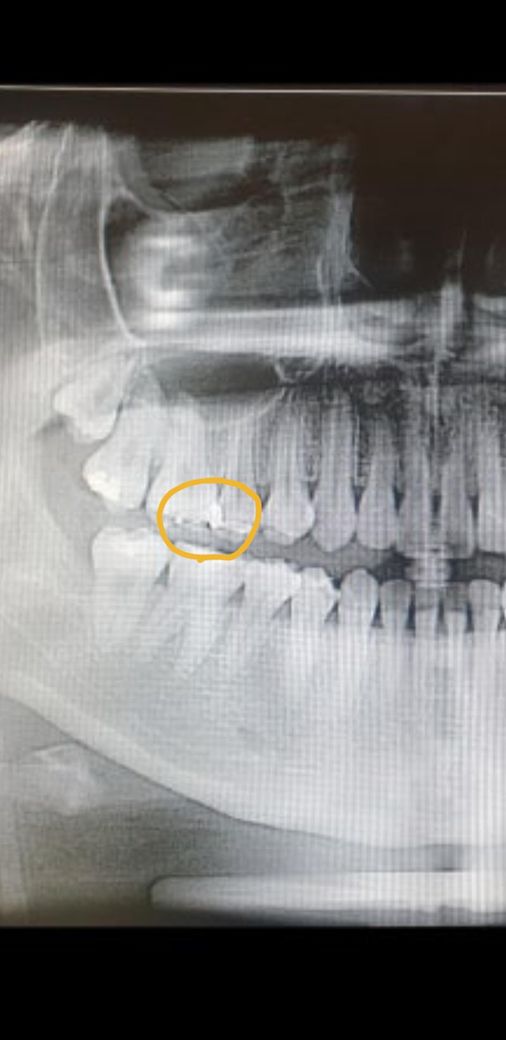

5~6년 전에 했던 금 인레이가 치실로 떨어질 수 있나요? 치실을 시작한지는 2~3년정도 됐는데 금 인레이를 사진처럼 두 치아에 인접면?에 걸쳐서 해놓은것 같아요 전에 치실할땐 별 증상 없다가 최근엔 인접면쪽에 치실을 넣을려고하면 잘 안들어가고 저 인레이가 걸리는 느낌이에요 혹시 뭔가 문제가 생겨서 갑자기 저러는걸까요? 2차충치 위험도 있을까요? 사진은 2년전에 찍었어요

1. 엑스레이 사진은 오래전이기도 하고 파노라마 방사선 사진이라 해상도가 떨어져서 큰 의미는 없을 것 같습니다.